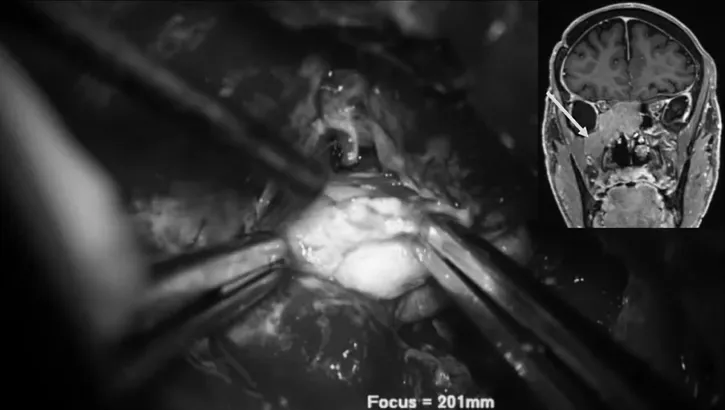

显微镜外科手术分步取出肿瘤图解

▼后颅窝部位肿瘤顺利切除

▼翼腭窝部位肿瘤顺利切除

▼翼腭窝到颞下窝部位肿瘤顺利切除

▼前内侧三角部位肿瘤切除

▼蝶窦部位肿瘤切除